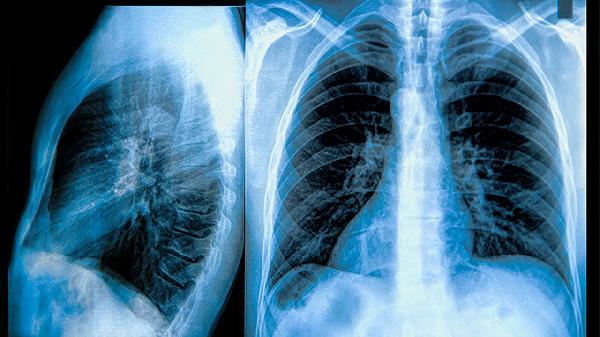

肺钙化本身极少直接影响寿命,其预后主要取决于原发病因及肺部功能状态。陈旧性肺结核导致的钙化灶若无活动性病变,通常无须特殊处理;职业性粉尘接触者需脱离污染环境并每年进行肺功能检测;慢性呼吸道疾病患者应接种流感疫苗和肺炎疫苗减少感染风险。钙化灶若伴随肺纤维化或慢性阻塞性肺病,可能出现咳嗽、活动后气促等症状,此时需通过低强度有氧运动维持肺功能。

建议每6-12个月复查高分辨率CT观察钙化灶变化,若出现新发结节、钙化灶增大或伴随胸腔积液等情况需及时就诊。日常可监测血氧饱和度,静息状态下低于95%时需评估肺功能。保持适度运动如快走、游泳等有氧活动,运动时心率控制在(220-年龄)×60%的安全范围内。出现不明原因体重下降、咯血或持续性胸痛时,应排除恶性肿瘤等继发病变。